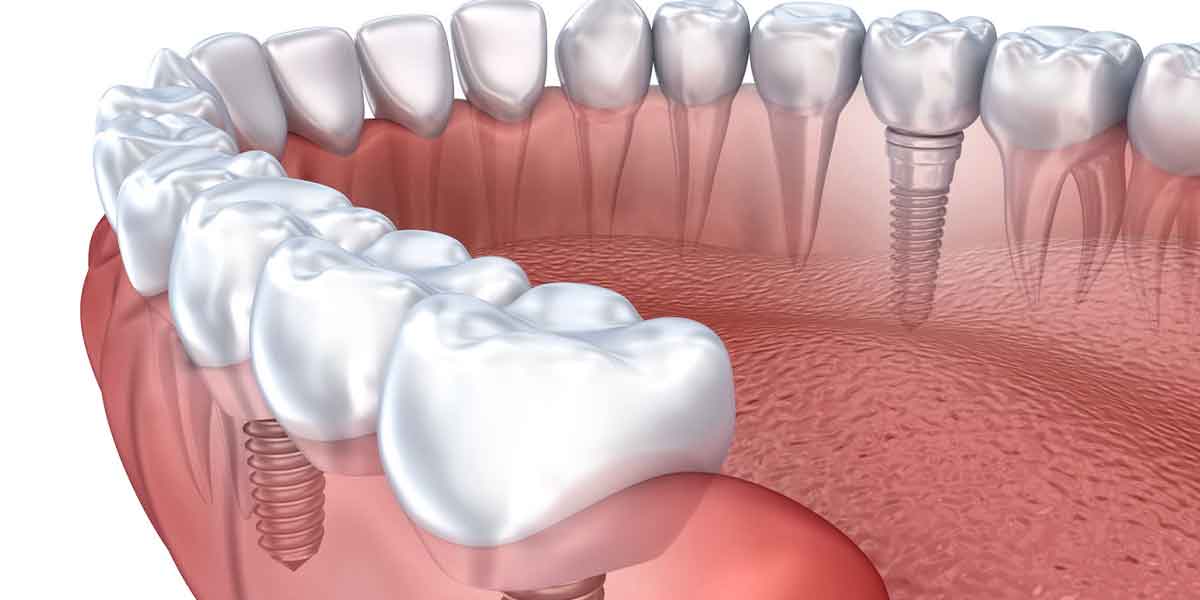

Dental implants are artificial tooth roots made of biocompatible materials such as titanium. They are surgically inserted into the jawbone, providing a stable foundation for replacement teeth, including crowns, bridges, or dentures. Dental implants mimic the function and appearance of natural teeth, offering a long-term solution for tooth loss.

Dental implants consist of three main components:

- Implant Fixture: The titanium post that is surgically placed into the jawbone, serving as the artificial root.

- Abutment: A connector placed on top of the implant fixture, holding the replacement tooth or teeth securely.

- Prosthesis: The visible part of the implant, which can be a crown, bridge, or denture.

Surgical Placement of the Implant

The next step is the surgical placement of the implant fixture. This procedure is typically performed under local anesthesia, although sedation options are available for anxious patients. The dentist will make an incision in the gum tissue, create a small hole in the jawbone, and insert the implant fixture.

After the implant is placed, a healing period of several months is required. During this time, the implant undergoes osseointegration, a process where the implant fuses with the jawbone, providing a strong and stable foundation for the replacement tooth.

Attachment of the Abutment

Once osseointegration is complete, the abutment is attached to the implant fixture. This minor procedure involves reopening the gum tissue to expose the implant and securing the abutment in place. The gum tissue is then allowed to heal around the abutment.

Placement of the Prosthesis

The final step is the placement of the prosthesis. Your dentist will take impressions of your teeth to create a custom crown, bridge, or denture that matches your natural teeth. The prosthesis is then attached to the abutment, completing the dental implant procedure.